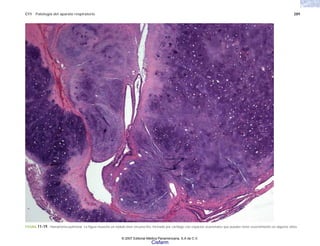

FIGURA 5-11. Diversos aspectos de la histología de la dermatitis por contacto. a) y b), formación de vesículas intraepiteliales en ausencia de infiltrado inflamatorio, c) hiperqueratosis, un

acompañante habitual de esta forma de dermatitis, d) las células basales epiteliales permanecen adheridas a las papilas; e) los anexos de la piel también están afectados.